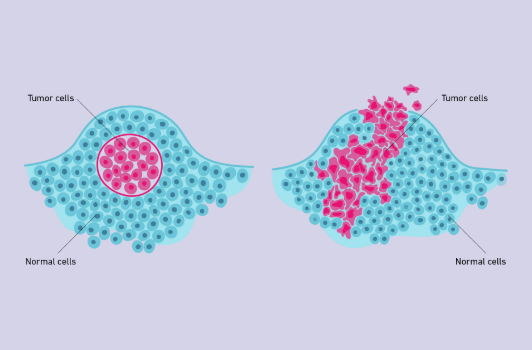

Benign Tumor

A tumor that does not affect surrounding tissues other than by physically crowding them (Left)

Malignant Tumor

A tumor that interferes with the functioning of surrounding cells; a cancerous tumor (Right)